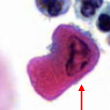

squamous cell carcinoma - tadpole cell